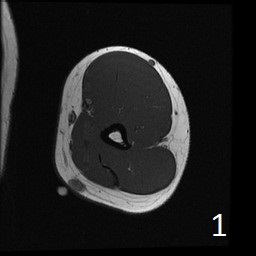

Angiolipoma is a subcutaneous benign tumor, made up of mature fat and blood vessels that often presents as multiple lesions. It sometimes arises intramuscularly. The incidence may be associated with familial heritage, close to 5% of the cases. Angiolipomas often arise in young patients, shortly before puberty, and are rarely seen in younger children or older adults. Angiolipomas often present as single or multiple subcutaneous tender to painful nodules (especially multiple ones). The pain may decrease as the lesion ages. No preference for ages or gender. Sites more commonly affected are the upper extremity and trunk, but rarely can affect head and neck region. MRI shows homogeneous and well circumscribed lesion, with intermediated signal on T1w (Fig. 1) and increased signal on T2W (Fig. 2). On fat suppress sequences the tumor may not suppress completely necause of its vascularity (Fig. 3). There is significant enhancement post contrast images (Fig. 4). On gross pathology the mass is a circumscribed, yellow-red nodular mass due high fat content and blood vessel proliferation. Microscopically, shows mature fat cells separated by branching network of small blood vessels, more prominent in subcapsular areas; there are usually associated fibrin thrombi (important sign). Adipocytes and interspersed vascular structures are seen, lined by elongated endothelial cells. These cells are irregular, and fingerlike extensions surrounded by periytes. Angiolipoma is a benign mass. It does not exhibit aggressive behavior. It rarely shows recurrence after resection. The treatment is complete surgical excision.

Fig. 1-4: Axial MRI of the arm shows a well circumscribed mass with intermediate signal on T1W (Fig. 1), and increased in T2W (Fig. 2). Fig. 3 Axial T1W FS shows a lesion and moderate intense on T1WFS post contrast (Fig. 4).